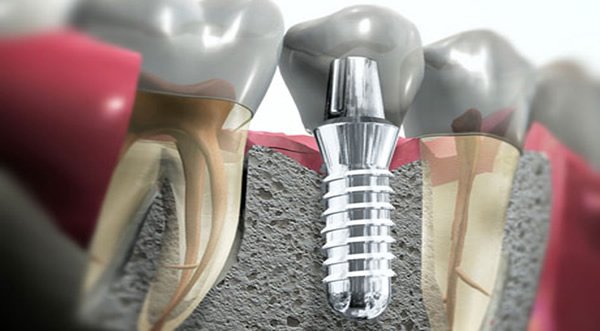

Chirurgia Implantare

L’implantologia permette ,attraverso l’utilizzo di strutture a forma di vite , di sostituire gli elementi dentari perduti. Gli impianti (le vitine che vengono posizionate nell’osso) sono molto versatili e consentono numerose soluzioni protesiche per sostituire gli elementi dentari perduti. Possono sostituire un singolo dente oppure possono essere utilizzati come pilastri per ponti fissi o come ancoraggio di protesi mobili.

L’implantologia permette ,attraverso l’utilizzo di strutture a forma di vite , di sostituire gli elementi dentari perduti. Gli impianti (le vitine che vengono posizionate nell’osso) sono molto versatili e consentono numerose soluzioni protesiche per sostituire gli elementi dentari perduti. Possono sostituire un singolo dente oppure possono essere utilizzati come pilastri per ponti fissi o come ancoraggio di protesi mobili.